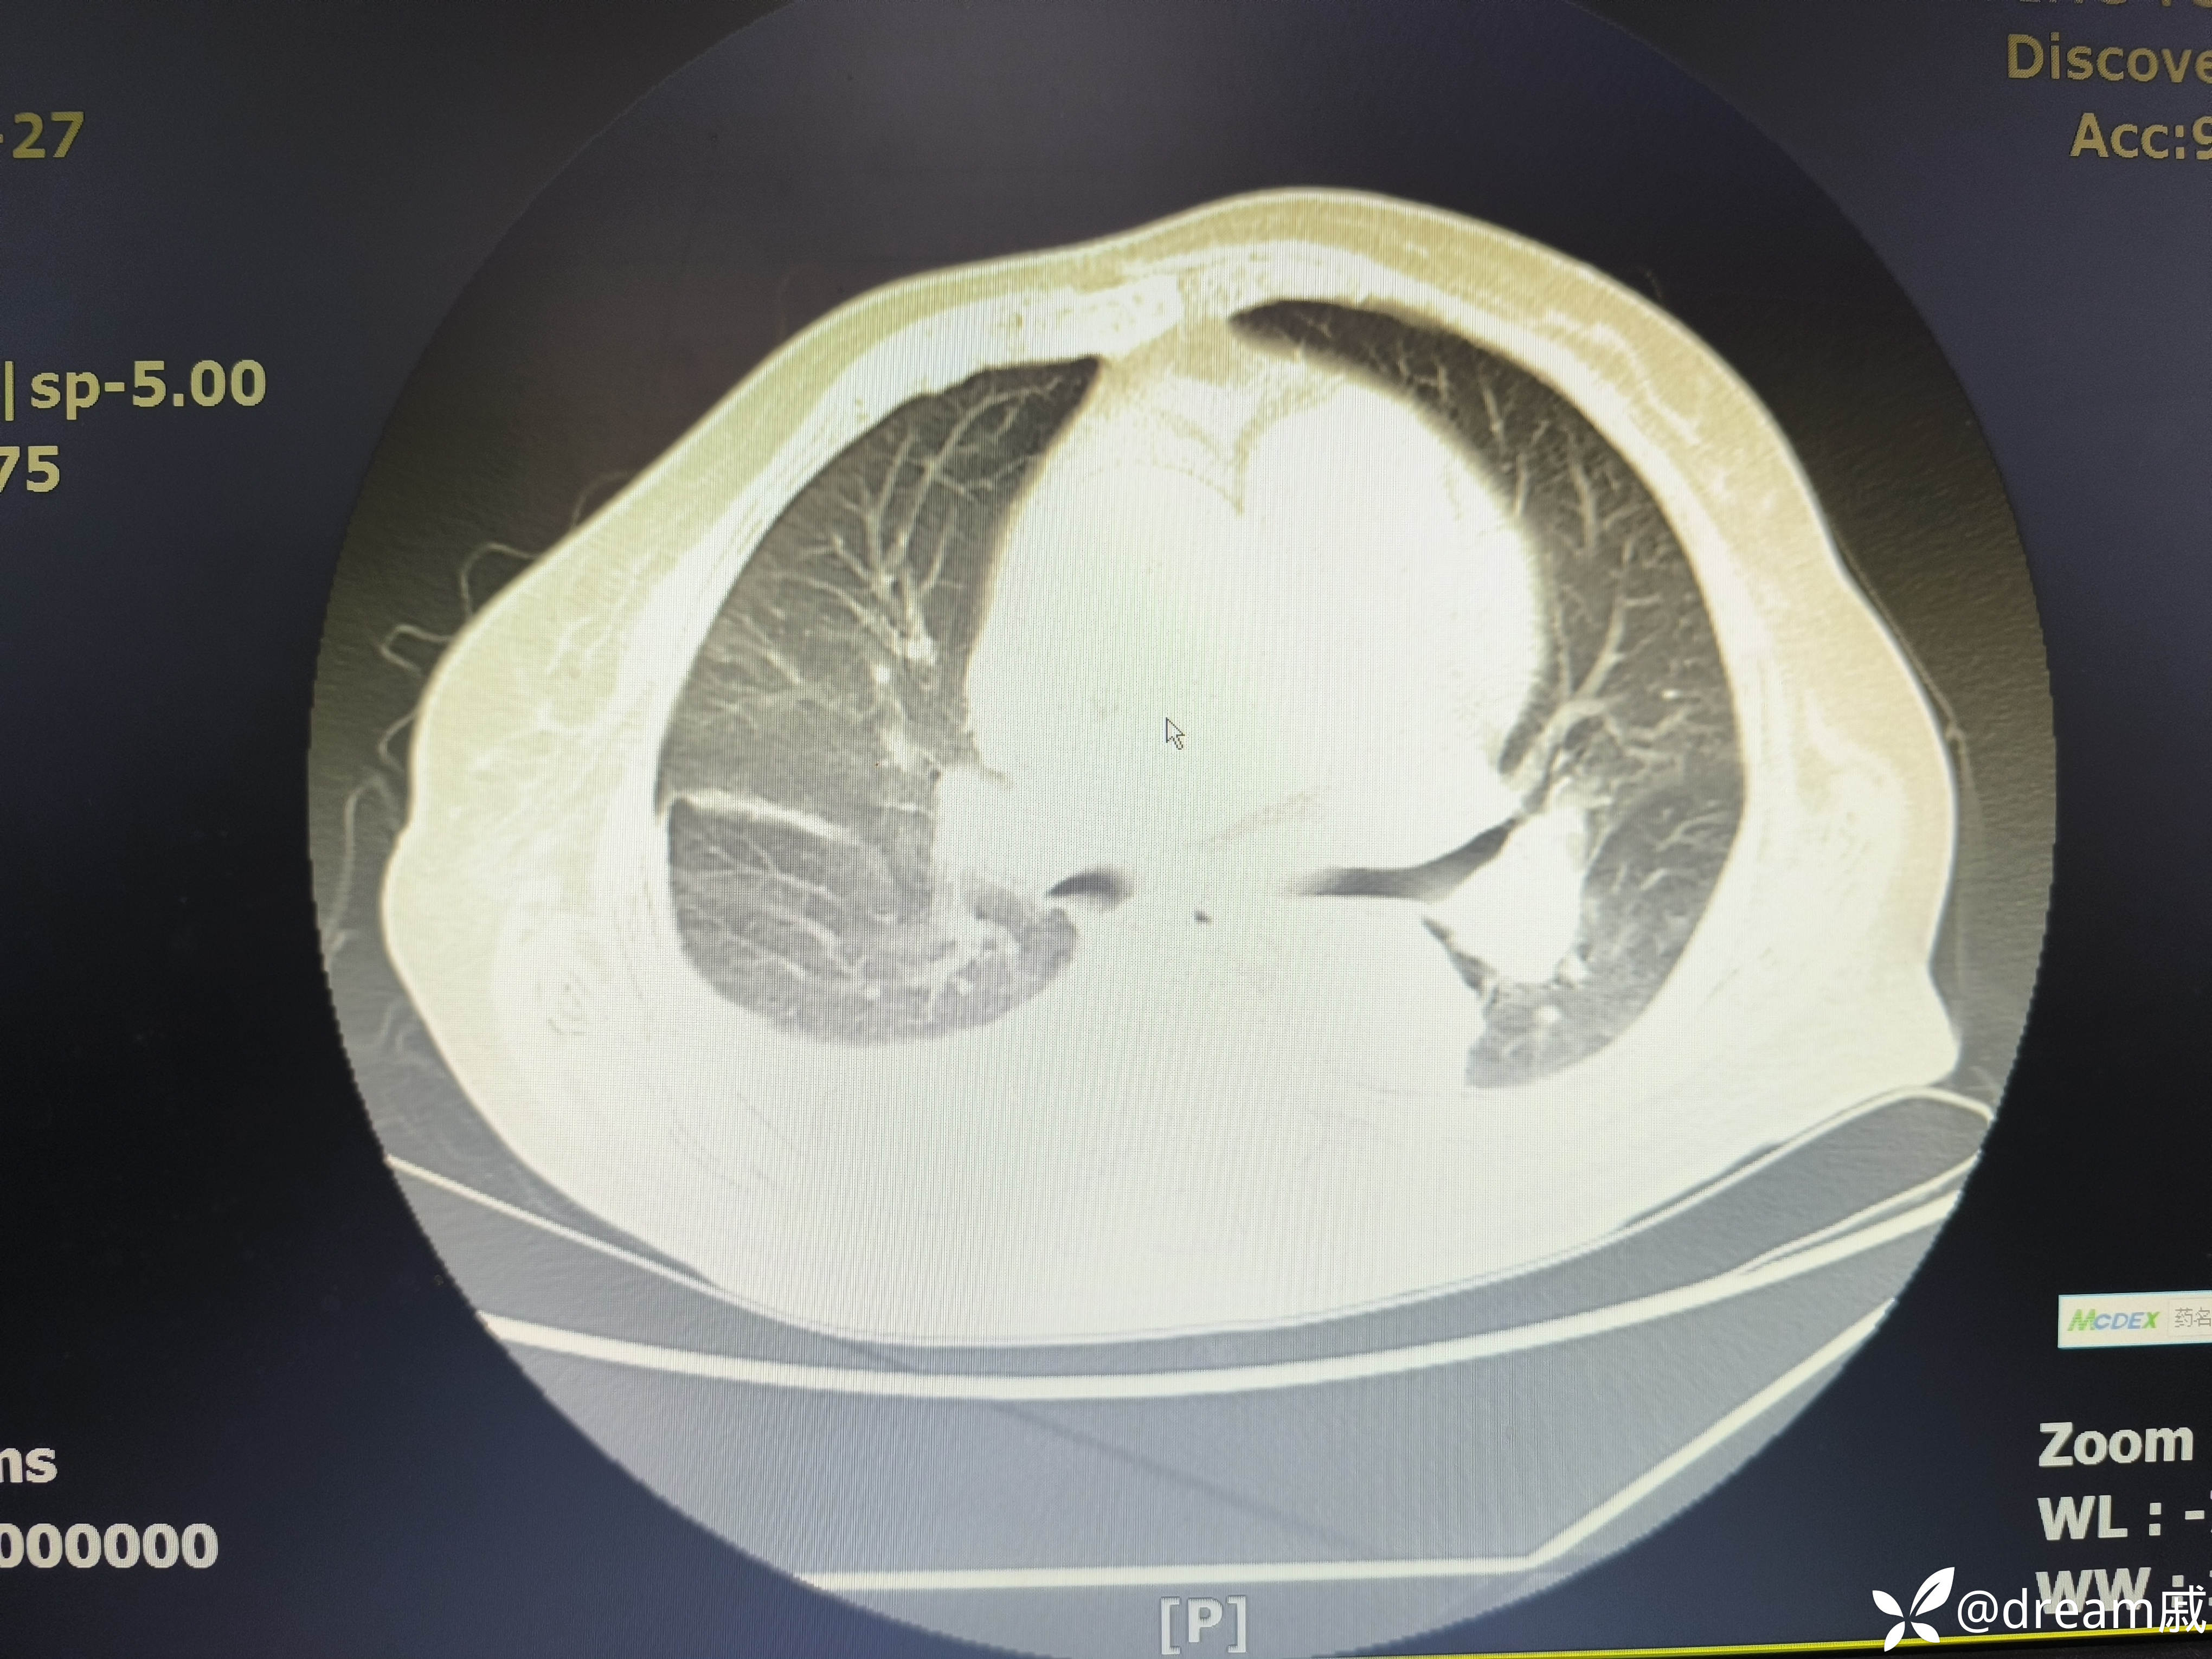

胸部CT示右肺中下叶斑片影,双肺局部间质性改变。

5月27日复查CT如下